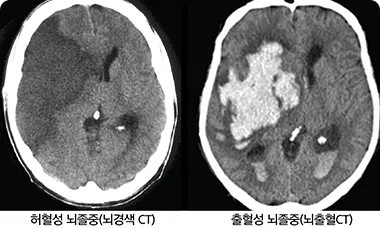

뇌혈관이 막히거나 터지는 질환을 부르는게 뇌졸중이고 그 중 뇌혈관이 막히는게 뇌경색 그리고 뇌혈관이 터지는 것을 뇌출혈이라고 합니다. 뇌졸중은 영구적인 손상이 많다고 하며 증상에 따라 전신이나 육체 일부 기능이 마비되는 등의 극심한 후유증이 남는 무서운 질병입니다 오늘은 뇌경색 초기증상에 대하여 알려드리도록 하겠습니다.

허혈성 뇌졸중은 발생 기전에 따라 대혈관 질환에 의한 뇌경색, 심인성 뇌경색 또는 심인성 뇌경색, 소혈관 질환 또는 틈새 뇌경색, 기타 드문 이유가 되는 것에 의한 뇌경색으로 나누어져요. 에피소드는 일정 기간 동안 증상이 완전히 가라앉는 경우입니다.

허혈성 뇌졸중의 대표적인 이유가 되는 것은 고혈압, 당뇨병, 고지혈증 등으로 인해서 뇌에 혈액을 전달하는 혈관에 동맥경화(동맥경화)가 발생하여 뇌로 가는 혈류를 차단하는 것입니다.